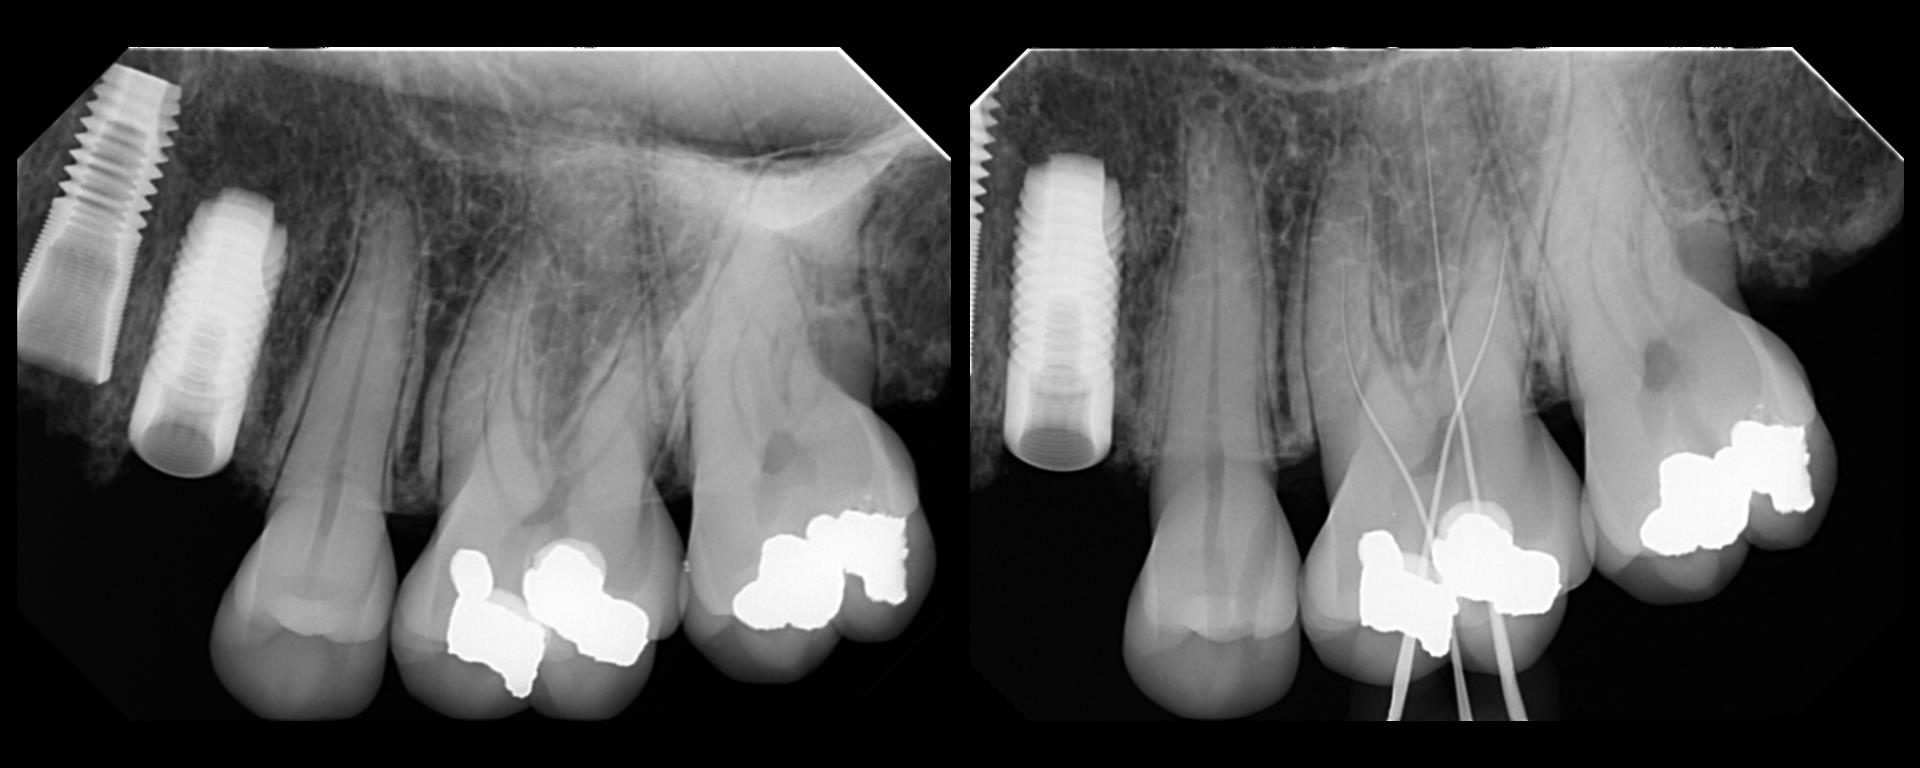

The discussion with James brought back memories of our original PERF CBCT project (that actually launched the CBCT revolution in endodontics, although no one gives us credit for that). Carlos Murgel, Peter Endo and I compared standard PA and CBCT imaging in many different ways. Standardizing the PA radiography was critical and proved to be […]